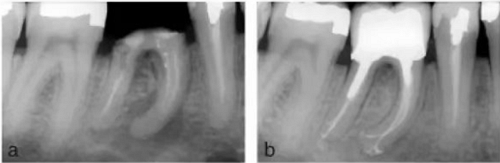

在白種人中,下頜第一磨牙主要為雙根—近中根和遠(yuǎn)中根,但其中根管形態(tài)各異。根據(jù)Vertucci 的分類,下頜第一磨牙中 59%的近中根在根尖處為獨(dú)立的雙根管,28%為兩根管融合成單根管單根尖孔,12%為單根管,1%為三根管(8,9)(圖 11a,b)。在另一項(xiàng)研究中,下頜磨牙的近中中根管(MM)發(fā)生率在 1%至 7%之間變化(92-99)。三個(gè)近中根管可以是獨(dú)立的(92-95)或融合稱為兩個(gè)根管,在根尖有兩個(gè)根管口(96-99)。

在歐洲人中,下頜第一磨牙的遠(yuǎn)中根大約 70%為單根管。15%為雙根管融合為單根管,5%為兩個(gè)獨(dú)立的根管,8% 為單根管分為雙根管,2%為單根管分為雙根管并再次于根尖1/3融合為單根管(8)(圖12a-b)。